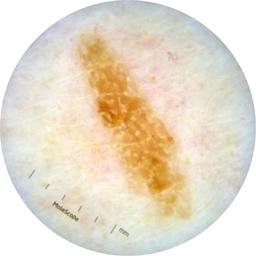

acquisition_day 254

age_approx 75

anatom_site_1 Trunk

anatom_site_2 Posterior trunk

anatom_site_general posterior torso

concomitant_biopsy False

diagnosis_1 Benign

diagnosis_confirm_type single image expert consensus

family_hx_mm True

image_type dermoscopic

personal_hx_mm True

sex male